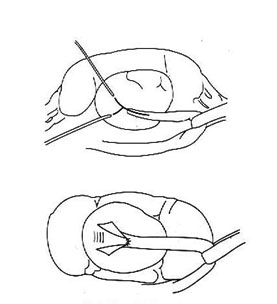

Y-V alakú 3.Pieloplastika (Foley)

8. ábra vonatkozó rendszer műanyagok ureter Foleyu